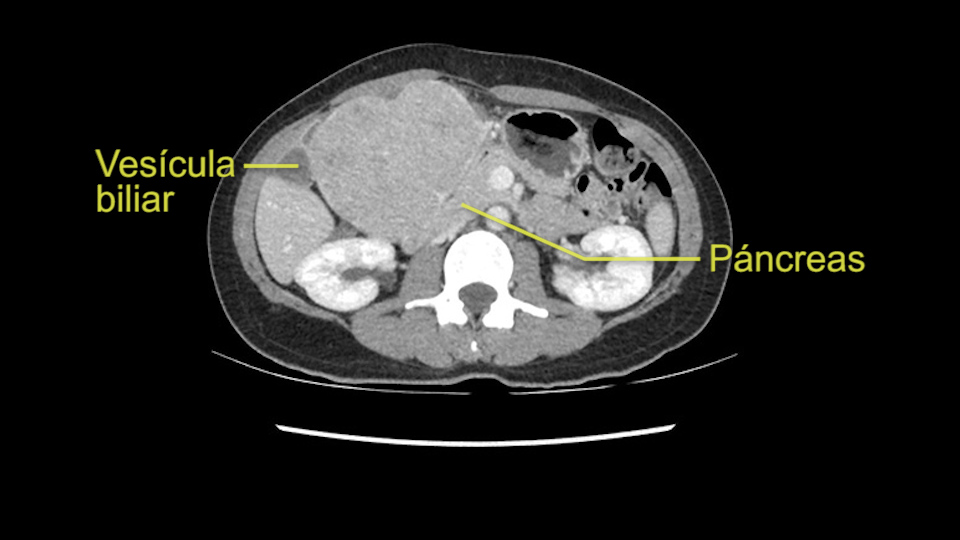

When you see the axial sections of the scan, you find it's a largely exophytic mass and its well-encapsulated. So this is typically true of a well-differentiated hepatocellular carcinoma. If you look at this, this is the gallbladder which is being displaced to the right and the mass is in the Sg4 of the liver, exophytic, projecting down. As it is coming down, it is also displacing the duodenum and the head of the pancreas which is being pushed towards the left and it's going right up to the cava, the start of the anterior surface of the cava. Obviously getting a lot of collaterals and vascularity from all the vessels around but one has to be very careful in evaluation of the main portal pedicle in this particular case and of course arterial inflow to the Sg4 and of course the left lobe of the liver.

Now coming to the duodenum, we can see that the stomach is coming down, and as it comes down to the head of the pancreas, it’s compressed by the mass which is distorting the duodenum completely. Is there invasion of the duodenum or not? When you see a little above, there is a very well nicely capsulated tumor so my impression is that it is only displacing the duodenum, may not be invading the duodenum. But however intraoperatively one has to be careful in dissecting the duodenum from the tumor.

So in planning for this operation, as I look at the scans, I first visualize the arterial phase and I can see that there’s are a lot of big feeding arteries to this large tumor. Likely all the right side vessels feeding the right side of the liver: right hepatic artery and likely the Segment 4 artery are spared from the tumor. It’s likely the left hepatic artery is ramificating and giving feeding arteries to this tumor. It certainly looks like a large mass that its compressing other structures like the cava, the pancreas, the stomach; but I think there’s a plane and we can see that better in the venous phase. There’s a plane of separation between the gallbladder, the pancreas, the cava, that this tumor is abrupting but likely not invading. Usually, these masses actually don’t invade at that level and basically are pushing the tissues and once you open, you’re able to separate the tumor. Sometimes there’s some adhesions but you can actually separate and there’s usually no invasion.

Lo siguiente que voy a hacer es mirar a la fase venosa. Y otra vez parece que todas las estructuras yendo al hígado derecho, es decir, tanto la vena porta derecha, la vena porta principal parece que están libres de tumor. Lo que si parce es que este tumor está comprimiendo diferentes estructuras, parece que comprime el páncreas, puede que este comprimiendo la cava, la vesícula biliar, pero en la mayoría de estos casos estos tumores no invaden estas estructuras, muy probablemente sea simplemente compresión, y una vez hallamos hecho la laparotomía es probable que todas estas estructuras queden separadas del tumor y puede que haya algunas adherencias que se puedan resecar sin problemas.